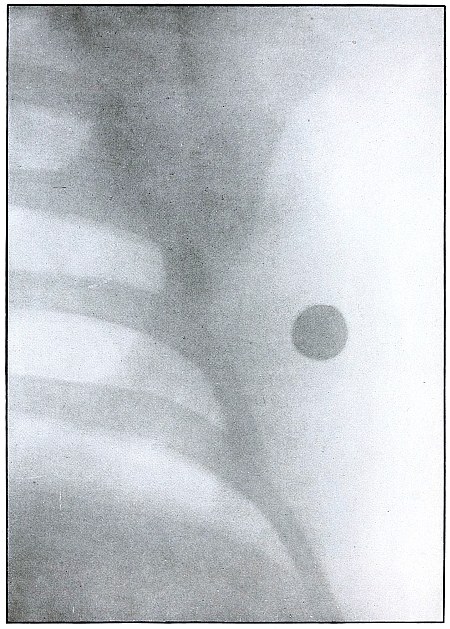

CHEST.

Plate 45.

[Pg 101]

Rifle—Plate 45.

CHEST.

Penetrating Gunshot Wound of the Chest,

with Lodgment of the Projectile Near Posterior Chest Wall.

Point of entrance, pectoral border and fourth rib.

Point of exit, none.

The distinct shadow of the angle of the ribs shows that the posterior

chest wall was next to the photographic plate, and that the larger and

less distinct outline of the anterior portions of the upper ribs was

farther from the plate.

The nearly normal size of the shadow of the projectile shows it to be

much nearer the posterior than the anterior chest wall. The blurred

outline shows it to have moved with respiration. Such conditions

locate its position within the thoracic cavity.

The emergency treatment is antiseptic dressing and rest.

The subsequent treatment depends upon pleural involvement or the

extremely rare infection of the lung.

These cases are nearly all aseptic, and if the great vessels and

nerves of the chest escape injury results are generally favorable.